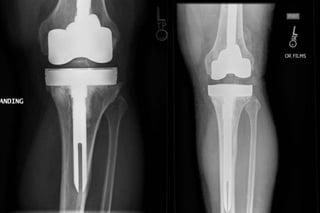

• 650,000 TKA per year (2010)

• 290,000 THA per year (2010)

–Kurtz et. al. JBJS AM 2014;96:624-630.

• Very high success rate (>90%)

• Significant positive impact on quality of life

• Widely successful

• Rapid improvement in pain/function (90%)

• Durable